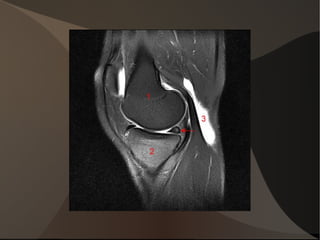

1/L'os: le soutien Observation des os qui constituent le genou

Image genou

Menisques Fibrocartilage.

Le même cartilage que celui du nez ou de l'oreille

2 ménisques posés sur les plateaux tibiaux

1 ménisque interne en forme de C et un ménisque externe en forme de O ouvert.

Les ligaments du genou Le pivot centrale:

- Ligament Croisé Antérieur: LCA